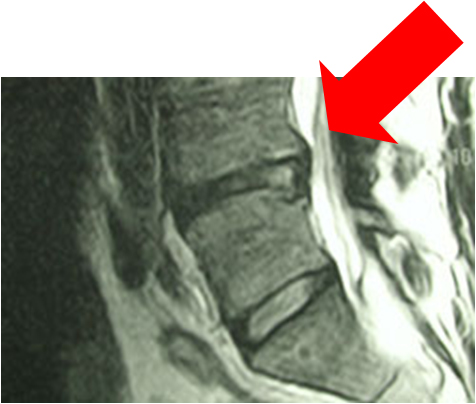

ΜαγνιτικÞ τομογραφßα πριν και μετα απü την επÝμβαση